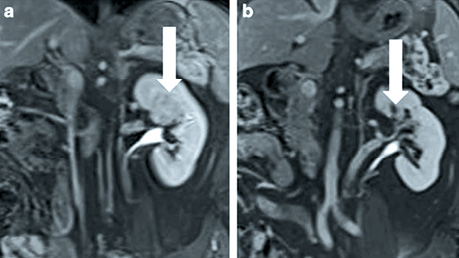

Контроль згідно з протоколом включає візуалізацію через 1 і 3 міс після лікування за допомогою МРТ і через 6 і 12 міс після терапії за допомогою КТ або МРТ (рис. 4) для пацієнтів з нирковою недостатністю або алергією на йодний контраст. Після цього всім пацієнтам щорічно проводиться КТ 3 зон для оцінки стану грудної клітки, черевної порожнини та малого таза протягом наступних 10 років.

Рис. 4. МРТ, екскреторна фаза на 12 хв після контрастного підсилення візуалізувала центрально розташовану пухлину розміром 3,5 см, біопсійно підтверджений еозинофільний нирково-клітинний рак (НКР) G1 (вертикальна стрілка) до НОЕ (а) і повне зникнення пухлини (вертикальна стрілка) через 12 міс після НОE (b) [цит. за 4]

Середній період спостереження становив 37 міс (12–62). У цій когорті НОЕ не втрачено жодного пацієнта для подальшого спостереження, а також не зафіксовано випадків 30-денної смертності після лікування. Однак зареєстровано 3 випадки смерті: серцева подія (n=1), метастатичний НКР (n=1) і геморагічний інсульт (n=1). Серед них у 2 пацієнтів розвинувся локальний рецидив захворювання в зоні абляції через 16 і 24 міс відповідно.

2- та 3-річна виживаність без метастазів у пацієнтів, які отримували НОЕ, становила 87% (95% ДІ 65%; 96%). Показники 2- та 3-річної канцерспецифічної (cancer-specific survival — CSS) та загальної виживаності у пацієнтів, які отримували НОЕ, становили 96% (95% ДІ 73%; 99%) та 89% (95% ДІ 70%; 96%).